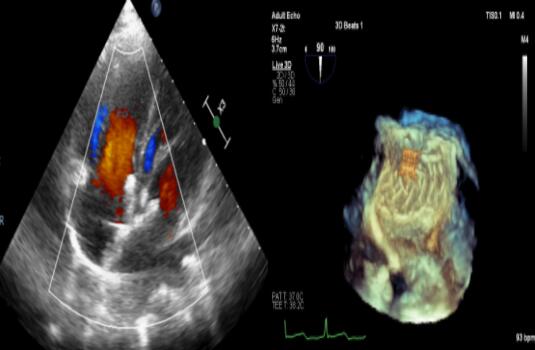

经胸和经食道实时三维超声心动图检测显示封堵器成形好,无残余分流

10月10日,广东省人民医院心血管病研究所张智伟主任手术团队、心内科费洪文主任配合经胸和经食道超声监测,演示了新型“生物可降解房间隔缺损封堵系统”介入手术,成功为两例房间隔膨出瘤合并多发缺损的患者实施经皮介入封堵手术,术后均无残余分流。